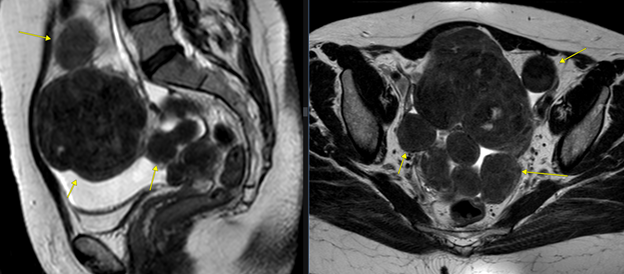

1. В полости малого таза определяются многочисленные однотипные объёмные солидные образования, преимущественно округлой формы, наиболее крупное - неправильной формы с бугристыми контурами, остальные - с ровными контурами, размером от 0.7х0.6 см до 8.1х8.6х8.8 см, преимущественно однородной структуры, тканевой интенсивности МР-сигнала, сравнимой с типичным сигналом от миометрия матки (рис. 1).

Рис. 1. Т2 ВИ sag/cor. Желтыми стрелками указаны однотипные объёмные образования с МР-сигналом, схожим с миометрием матки.